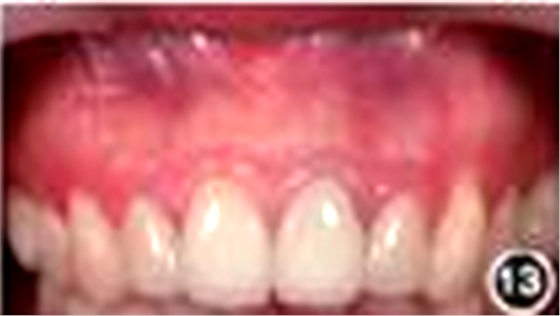

6.再治疗术后2年复查:

见图12,图13。临床检查叩诊正常,不松动,牙龈色泽正常,切口位置可见隐约瘢痕。根尖X线片显示根尖无明显病变。

图13 患者术后2年复查口内照片